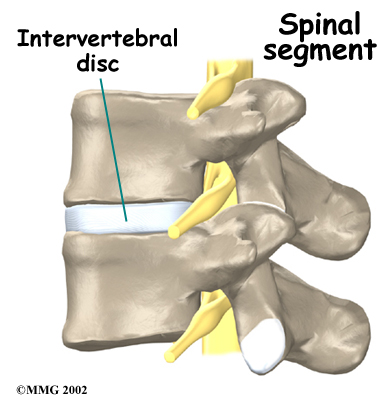

Intervertebral discs separate the vertebral bodies. The discs normally work like shock absorbers. They protect the spine against the daily pull of gravity. They also protect the spine during strenuous activities that put strong force on the spine, such as jumping, running, and lifting.

Between the vertebrae of each spinal segment are two . The facet joints are located on the back of the spinal column. There are two facet joints between each pair of vertebrae, one on each side of the spine. A facet joint is made of small, bony knobs that line up along the back of the spine. Where these knobs meet, they form a joint that connects the two vertebrae. The alignment of the facet joints of the lumbar spine allows freedom of movement as you bend forward and back.

The anatomy of the lumbar spine is often discussed in terms of . Each spinal segment includes two vertebrae separated by an intervertebral disc, the nerves that leave the spinal cord at that level, and the facet joints that link each level of the spinal column.